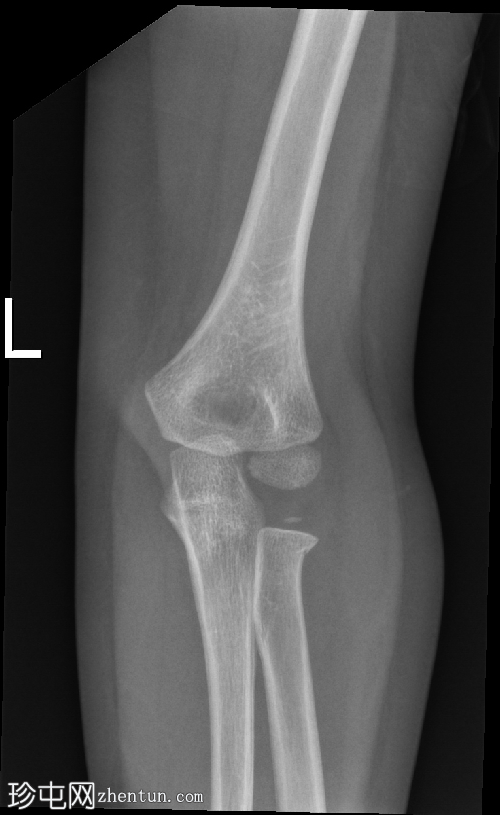

X光片

2.png

侧面

在正位片和侧位片上,桡骨近端干骺端可见轻微的皮质断裂和不规则,骨折线似乎向骺端延伸。

相关的脂肪垫征(可见前脂肪垫和帆状征,后脂肪垫阳性)进一步支持骨折后关节内积液的存在。

总体而言,骨性对线保持良好,无脱位迹象。

骨化中心与年龄相符。